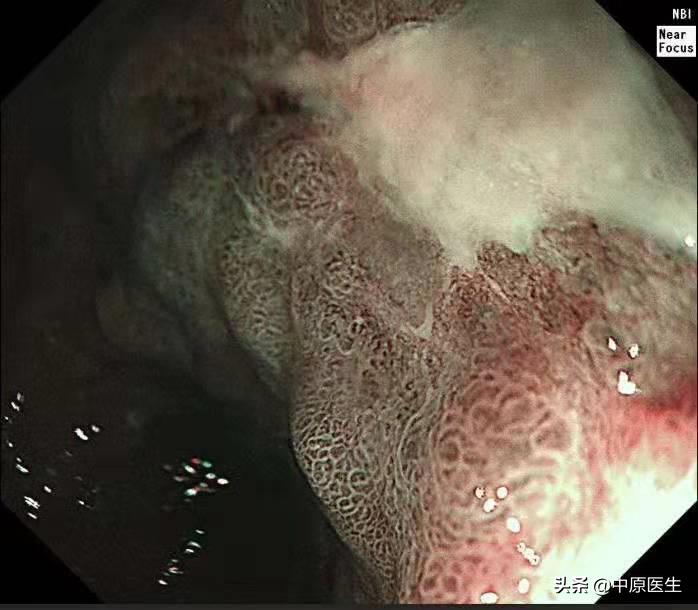

这个患者的溃疡多发,不算太大,并且表面的苔很干净,底部也算平坦,尤其是新发现的两个溃疡,从这几个条件来看,似乎良性可能性大。但是,我还是不放心。我现在只是用了白光检查,为什么不选择窄带光,放大检查?虽然麻烦一点,但是,可以看到更多细节!于是,我打开NBI模式,并且使用变焦(俗称放大,可以达到和显微镜下看类似的效果),再仔细地对每一处病变进行了观察,结果竟然发现,虽然范围很小,尤其是胃窦处的溃疡,不超过2个毫米的范围内我都发现了腺管缺失和血管异常扩张的地方,这往往提示病变有可能已经癌变,在放大镜的引导下,我对病变进行了精准活检。

周一上午,病理出来了,结果触目惊心,每一处溃疡都取到了癌组织,至此该患者诊断明确,他已经不是胃镜可以切除的早期胃癌,更不是良性的胃溃疡,而是需要进行外科手术切除的胃癌!